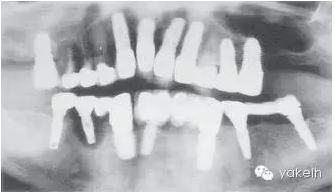

該病例全頜曲面斷層片顯示(圖.13)種植體修復(fù)存在一系列問題。LR5種植體周圍骨組織完全喪失,LL3發(fā)生了種植體周圍炎,LL6冠與基臺(tái)未完全密合。

圖13 全頜曲面斷層片進(jìn)一步證實(shí)LR5種植失敗,其他種植體存在種植體周圍炎以及修復(fù)體與基臺(tái)不密合。